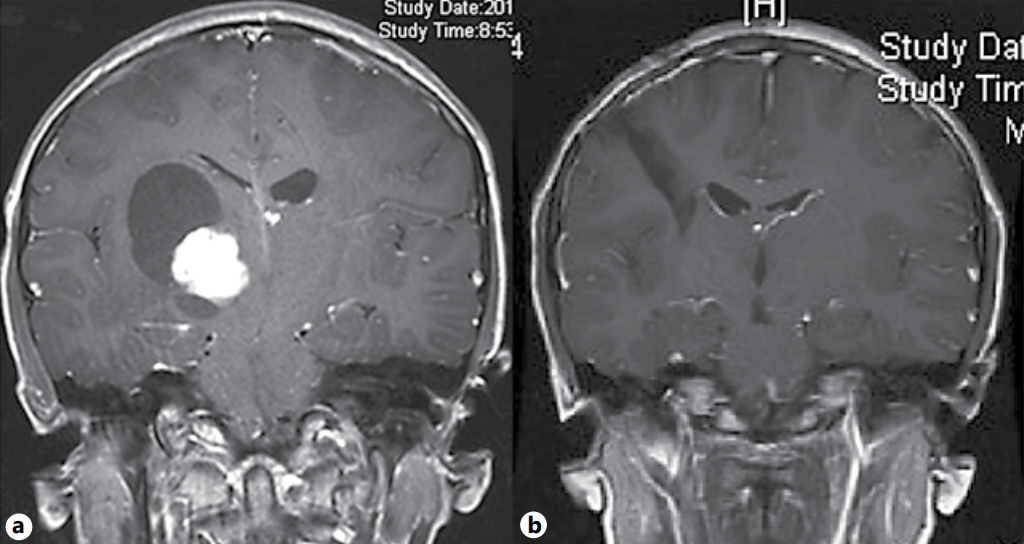

对于低度胶质瘤,手术仍是优选,应直接在有利部位进行全切,如大脑半球和小脑。高级别胶质瘤(HGG)的治疗仍然是一个的挑战,它在儿童中的发病率低于成人。在非脑干高级别胶质瘤中,目标是顺利较大限度地切除肿瘤,而在弥漫性固有性脑桥胶质瘤中一般不起任何作用。因此,在大多数高级别胶质瘤病例中,治疗需是个体化的。儿童脑胶质瘤的手术继续受到促进肿瘤切除和提高患者顺利性和预后的技术进步的帮助。

该论文简介中指出,胶质瘤是根据其位置和国际卫生组织(WHO)的组织病理学分级进行分类的,这两个因素对该病的评估都是重要的。儿童年龄组较为常见的脑肿瘤是良性低度胶质瘤(LGG),包括毛细胞性星形细胞瘤(PA)和室管膜下巨细胞星形细胞瘤(WHO 1级)和弥漫性星形细胞瘤(WHO 2级)。与成人相比,与世卫组织病理学分级3(如间变性星形细胞瘤)和4级(多形性胶质母细胞瘤)相对应的高级别胶质瘤(HGG)在儿童中较少见。这些肿瘤和弥漫性固有性脑桥胶质瘤(DIPG)约占全部儿童脑肿瘤的20-25%。高级别胶质瘤在婴儿期很少见,但随着年龄的增长,高级别胶质瘤的发病率逐渐上升,在青少年中发病率较高。

James T. Rutka教授在该论文结论中指出,儿童年龄组的脑胶质瘤手术对儿童神经外科医生来说是一个较大的挑战。结果主要取决于年龄,肿瘤位置,组织学和手术切除程度。治疗应该是个性化的和基于多学科的方法,而外科医生应该利用现有的技术辅助手段来好转这些病人的护理。